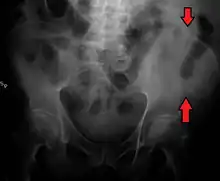

A fracture of the left iliac wing

The iliac crest has a large amount of red bone marrow, and thus it is the site of bone marrow harvests (from both sides) to collect the stem cells used in bone marrow transplantation. The iliac crest is also considered the best donor site for bone grafting when a large quantity of bone is needed. For example, oral and maxillofacial surgeons will often use iliac crest bone to fill in large osseous defects of the oral cavity caused by severe periodontal disease, excess bone resorption following tooth loss, trauma, or congenital defects including alveolar clefts.[4]